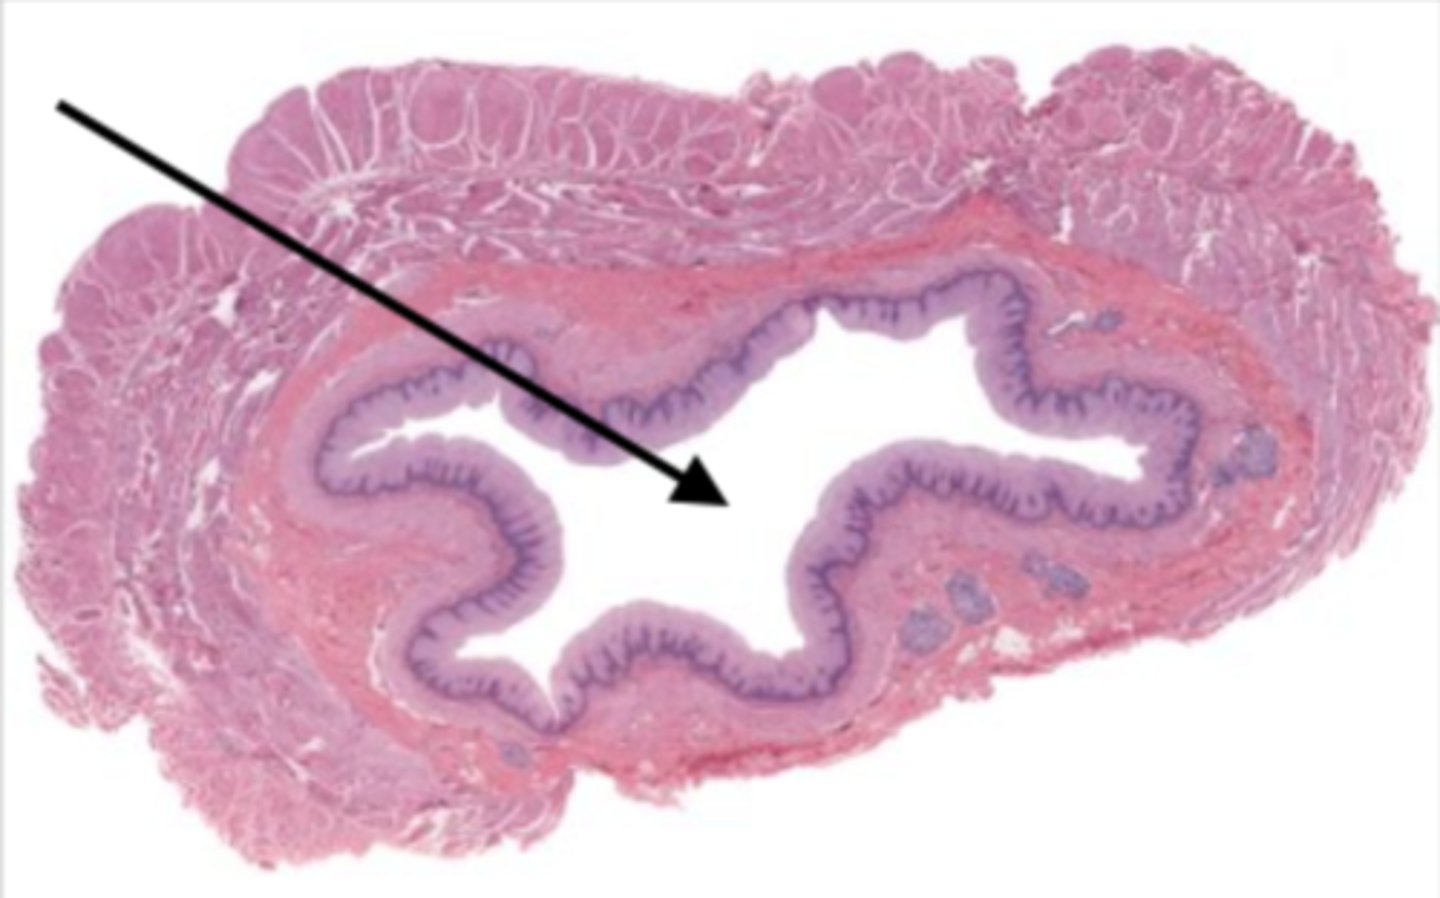

colon (histology)

simple columnar epithelium

what kind of epithelium lines the mucosa of the colon?

intestinal glands/crypts (colon)

lumen (colon)

mucosa (colon)

mucosal epithelium (colon)

lamina propria (colon)

muscularis mucosa (colon)

submucosa (colon)

contains glands and blood supply

muscularis externa (colon)

serosa/adventitia (colon)